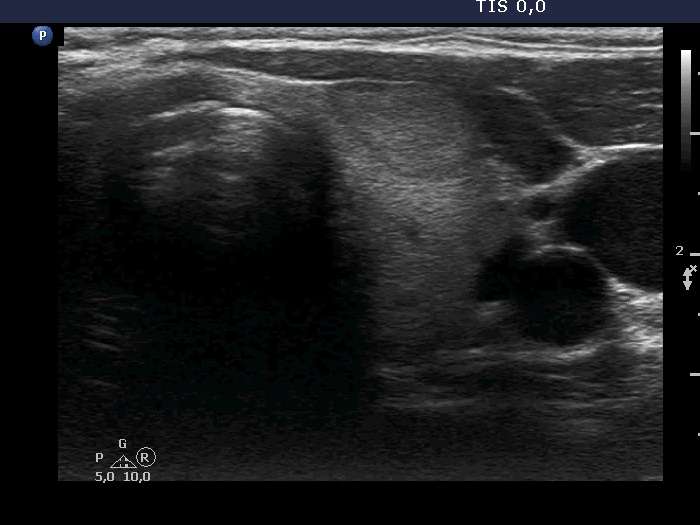

Ultrasonography. The thyroid was echonormal and hand numerous nodules. The nodule in the right side of the isthmus was the only one which increased over the last seven years.

Comment. It is worth analyzing the nodule in the right lobe which has echogenic granules. These figures are clearly back wall ones caused by posterior cystic enhancement.